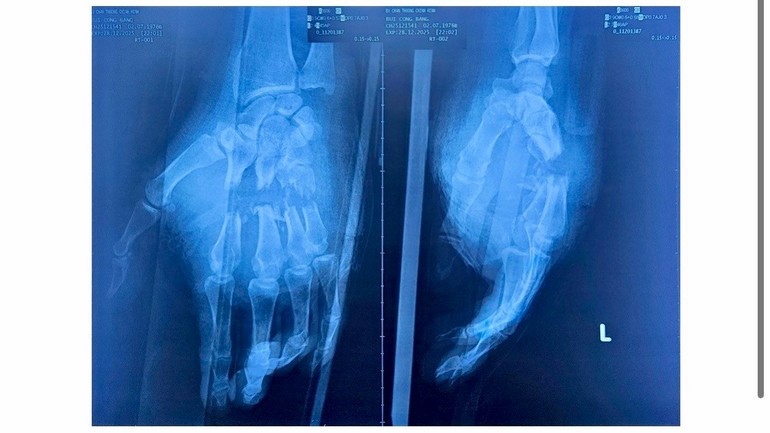

Bệnh nhân B. sinh năm 1976, ngụ tại Đặc khu Phú Quốc, tỉnh An Giang là công nhân lao động. Trong lúc làm việc vào cuối tháng 12/2025, bệnh nhân không may bị máy cưa gỗ gây tai nạn nghiêm trọng làm đứt gần lìa bốn ngón tay II, III, IV, V của bàn tay trái. Đây là tổn thương phức tạp, nguy cơ mất hoàn toàn chức năng bàn tay nếu không được xử trí kịp thời và đúng kỹ thuật.

Sau khi được sơ cứu ban đầu, bệnh nhân được chuyển đến Bệnh viện Chấn thương chỉnh hình Thành phố. Qua thăm khám, cho thấy vết thương kéo dài từ mặt lòng đến mặt lưng bàn tay, gãy hở nhiều xương bàn ngón, đứt toàn bộ gân, mạch máu và thần kinh của bốn ngón tay, các ngón tím lạnh, mất hoàn toàn vận động và cảm giác.

Hình ảnh chụp phim cho thấy nhiều xương ngón tay bị gãy hở.

Các bác sĩ nhận định đây là tình trạng cấp cứu ngoại khoa nặng, phải chạy đua từng phút để giữ lại bàn tay cho người bệnh. Ngay lập tức, ca phẫu thuật được tiến hành kéo dài trong 6 giờ. Ê-kíp đã cắt lọc, xuyên đinh Kirschner cố định xương, nối gân gấp sâu, gân duỗi và thực hiện nối vi phẫu nhiều nhánh động mạch, tĩnh mạch dưới kính hiển vi.